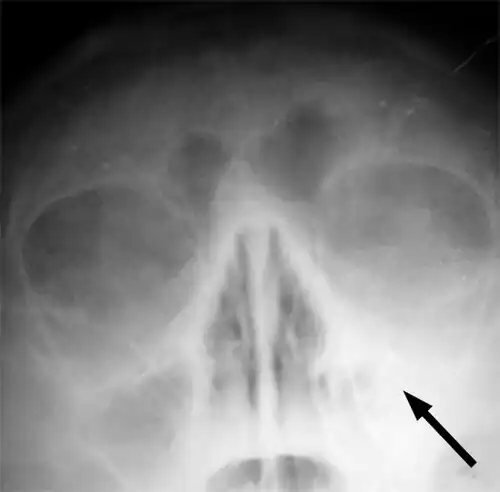

Imaging by either X-ray, CT, or MRI is generally not recommended unless complications develop.[66] Pain caused by sinusitis is sometimes confused for pain caused by pulpitis (toothache) of the maxillary teeth, and vice versa. Classically, the increased pain when tilting the head forwards separates sinusitis from pulpitis.[68]

For cases of maxillary sinusitis, limited field CBCT imaging, as compared to periapical radiographs, improves the ability to detect the teeth as the sources for sinusitis. A coronal CT picture may also be useful.[60]

Chronic

For sinusitis lasting more than 12 weeks, a CT scan is recommended.[66] On a CT scan, acute sinus secretions have a radiodensity of 10 to 25 Hounsfield units (HU). In a more chronic state, they become more viscous, with a radiodensity of 30 to 60 HU.[69]

-

CT of chronic sinusitis -

CT scan of chronic sinusitis, showing a filled right maxillary sinus with sclerotic thickened bone -

MRI image showing sinusitis. Edema and mucosal thickening appear in both maxillary sinuses. -

Maxillary sinusitis caused by a dental infection associated with periorbital cellulitis -

Frontal sinusitis -

X-ray of left-sided maxillary sinusitis marked by an arrow. There is a lack of air transparency, indicating fluid in contrast to the other side.